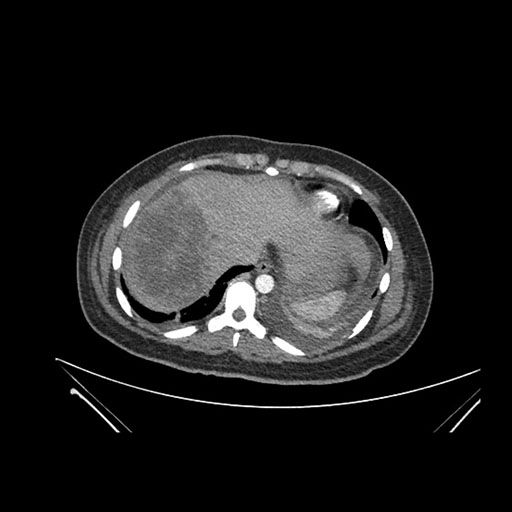

Imaging Analysis

Look through the patient's CT scan to identify any areas of concern for the necessary procedure.

Axial Venous

Based on initial findings, which issue(s) would you be most concerned about?